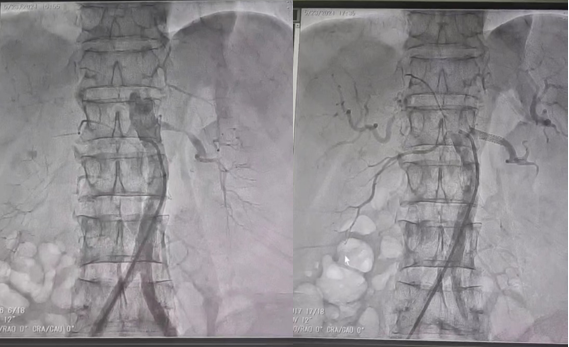

西咸院区肾内科就诊。王琼主治医师在诊查中发现患者肾功能中度损伤伴高血压及高钾血症,血压高达180/90mmhg,肾脏超声提示左肾动脉起始段明显纤细。考虑到左肾动脉局部明显狭窄,严重影响肾灌注及功能,但行传统的外科手术治疗创伤大,恢复慢,患者接受度低,结合患者情况,闫晓辉副主任医师和微创介入科陈思攀主任详细评估病情后,为患者制定了安全、有效的微创手术方式,即“左肾动脉造影及成形术”。医患双方充分沟通,并取得患者及家属的同意后,手术由微创介入科团队完成。在进行了多角度肾动脉造影后,精准测量左肾动脉狭窄段的长度、形态等参数,通过纤细导管将肾动脉专用支架送入肾动脉狭窄段,再次造影确认肾动脉狭窄段消失,血流明显恢复通畅,手术顺利结束。患者安返病房。